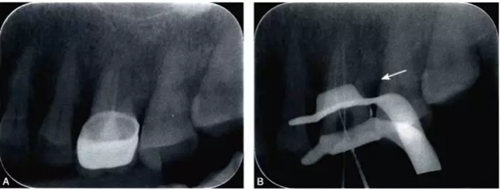

完全鈣化根管在X線片上的表現(xiàn)是根管影像模糊,密度增高,根管密度與周圍的牙本質(zhì)密度接近,甚至無法區(qū)分根管與牙本質(zhì)的影像。有些根管,可表現(xiàn)為根管影像時斷時續(xù)或模糊不清,為不完全鈣化根管表現(xiàn)(圖4-1A)。細(xì)小根管的病例在X線片上,根管影像隱約可見,與同名牙或鄰牙相比,根管較為細(xì)小影像清晰度降低。

細(xì)小鈣化根管的根管口,即使是在口腔手術(shù)顯微鏡下,也不容易被發(fā)現(xiàn)。在鈣化根管的早期,鈣化牙本質(zhì)的顏色可能與周圍正常牙本質(zhì)不同,因此,多數(shù)情況下,利用口腔手術(shù)顯微鏡能夠發(fā)現(xiàn)根管所在位置。有的鈣化根管牙本質(zhì)與周圍牙本質(zhì)顏色相似,難以區(qū)分,此時借助手術(shù)顯微鏡的高倍放大作用,結(jié)合根管解剖知識,仔細(xì)觀察顏色的細(xì)微差異,有助于提高探查根管口的成功率。完全鈣化的根管,表現(xiàn)為均質(zhì)的硬組織結(jié)構(gòu),有時與正常牙本質(zhì)結(jié)構(gòu)難以區(qū)別,當(dāng)采用各種方法均無法疏通時,為了避免產(chǎn)生新的并發(fā)癥,不宜強行疏通,可定期追蹤觀察(圖4-2)